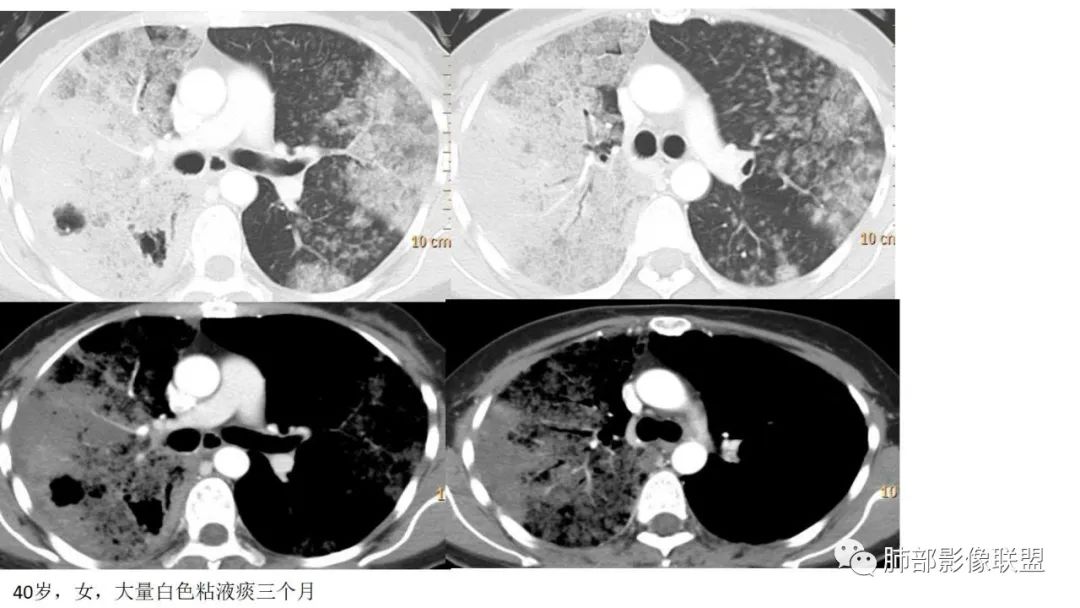

1、患者有咳白色泡沫状黏液痰的病史,患病时间较长。病理阴性不能排除。

2、病灶常有一个主病灶,常位于下肺。后沿气道播散为多发病灶。

9.粘液腺癌的变化规律:结节缓慢发展而来,向周围播散形成斑片后可快速进展,有时支气管镜后或粘液排出后局部可形成好转的假象。病灶可沿肺泡和支气管播散。

4.回到本例,左下肺病变两次好转,均未经过肿瘤治疗,第一次是支气管镜后,第二次是当其他病变都在进展的情况下,左下肺病变范围反而缩小趋于浅淡。